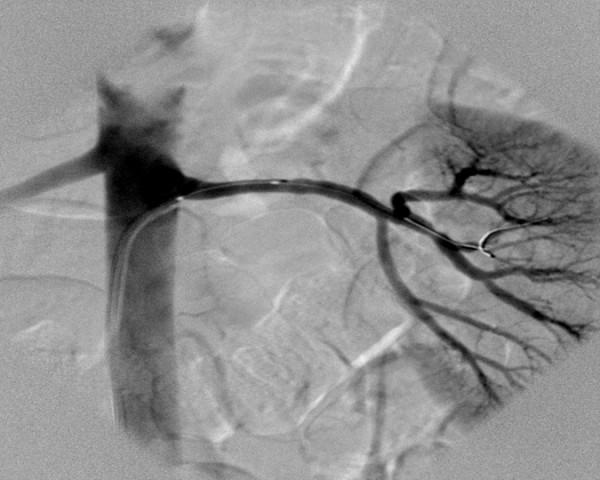

In this report, we present a relatively uncommon case of renovascular hypertension in a 35-year-old female with a history of intractable hypertension as a result of fibromuscular dysplasia involving an accessory renal artery. Selective renal angiography was performed and revealed a single renal artery on the right and two renal arteries supplying the left kidney, upper and lower poles. Selective renal angiography showed the typical fibromuscular dysplasia lesion characterized by its classic "string of beads" appearance, consisting of alternating areas of narrowing and dilatation, located in the middle portion of the lower left renal artery (accessory artery) associated with moderate stenosis. Percutaneous balloon dilatation of the stenotic lesion was successfully performed. Following angioplasty, her blood pressure normalized over a period of several months using a single antihypertensive medication (rather than 3 medications).

在本报告中,我们呈现了一例相对罕见的肾血管性高血压病例,患者为一名35岁女性,有顽固性高血压病史,病因是累及副肾动脉的纤维肌发育不良。进行了选择性肾血管造影,结果显示右侧有一条肾动脉,左侧肾脏的上极和下极由两条肾动脉供血。选择性肾血管造影显示典型的纤维肌发育不良病变,其特征为经典的“串珠样”表现,由狭窄和扩张交替区域组成,位于左肾下极(副肾动脉)中部,伴有中度狭窄。成功地对狭窄病变进行了经皮球囊扩张。血管成形术后,她仅使用一种抗高血压药物(而非三种药物),血压在几个月内恢复正常。